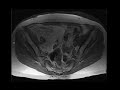

Retroperitoneal liposarcoma

Patient with abdominal pain. MR and CT images demonstrate a large fat containing mass in the right anterior pelvis with internal complexity and nodular soft tissue, in keeping with a retroperitoneal liposarcoma.